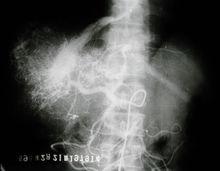

巨大肝臟腫瘤 一、各種病原體感染。包括病毒、細菌、寄生蟲等感染。如最常見的病毒性肝炎;還有如細菌感染引起的肝膿腫、肝結核,寄生蟲感染引起的肝吸蟲病、阿米巴肝膿腫等等。